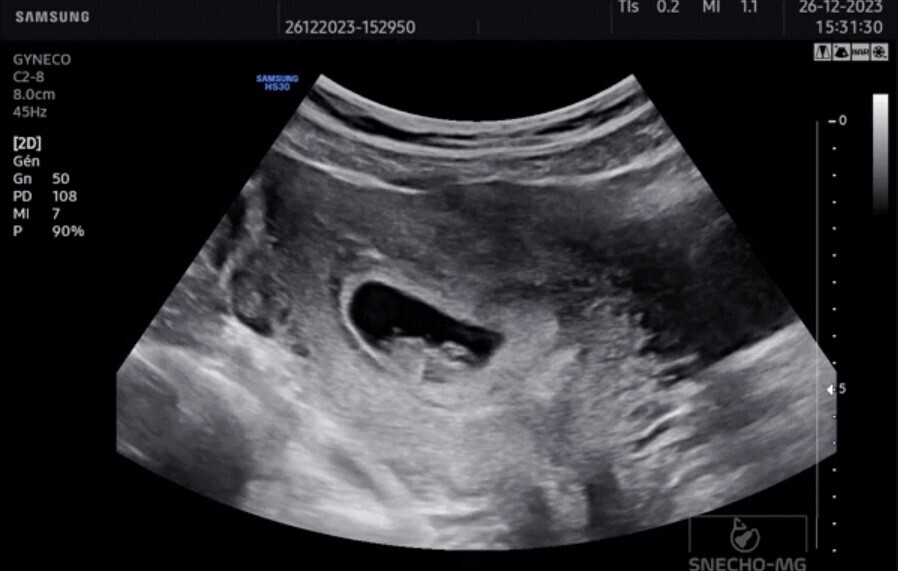

L’échographie peut ainsi, par exemple, aider au diagnostic devant une douleur abdominale (colique hépatique, colique néphrétique...), une douleur pelvienne (torsion ovarienne, grossesse extra-utérine...), une masse sous-cutanée, une suspicion de rupture tendineuse ou de nodule thyroïdien clinique, ou en cas de toux…

En 2023, les Drs Louis Camard et Mariela Skendi ont réalisé un travail sur une liste de compétences en échographie clinique ciblée.5 Le premier niveau concerne surtout la recherche des signes de complication et d’urgence quand l’examen clinique n’est pas suffisant pour poser un diagnostic. Mais ces compétences peuvent s’enrichir en fonction du niveau de formation du médecin et concerner différents domaines, comme les troubles hépatobiliaires, urinaires, gynéco-obstétricaux, vasculaires… Cette liste n’est pas exhaustive et peut s’étendre à d’autres domaines, selon les appétences du médecin : troubles musculosquelettiques, pulmonaires et des parties molles.